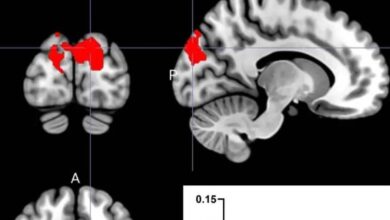

“ديكستروميثورفان” (DXM) من مثبطات السعال الشائعة، وقد أظهرت مراجعات أنه من أكثر الأدوية المتاحة دون وصفة تعرضا لسوء الاستخدام. وعند تناول جرعات عالية، يثبط مستقبلات NMDA في الدماغ، ما قد يؤدي إلى تأثيرات انفصالية مشابهة للكيتامين (دواء يُستخدم طبيا كمخدر ومسكّن للألم). ورغم أمانه عند الالتزام بالجرعات الموصى بها، فإن تأثيراته النفسية تثير القلق بشأن إساءة استخدامه.